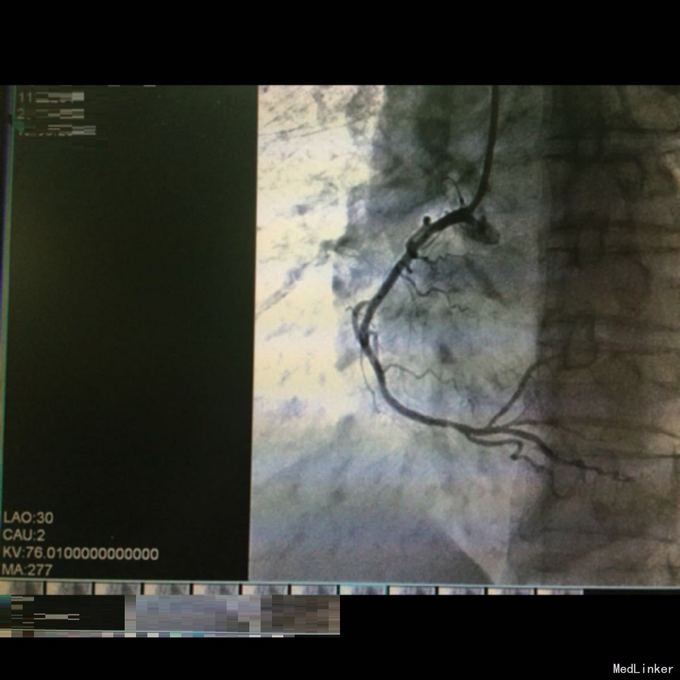

查体:生命体征平稳。双肺呼吸音粗,双下肺可闻及湿性啰音。 辅查:急诊CAG+PCI见右冠近段狭窄约90%,遂置入药物支架一枚,造影显示远端血流达TIMI3级。复查心电图示下璧心梗。